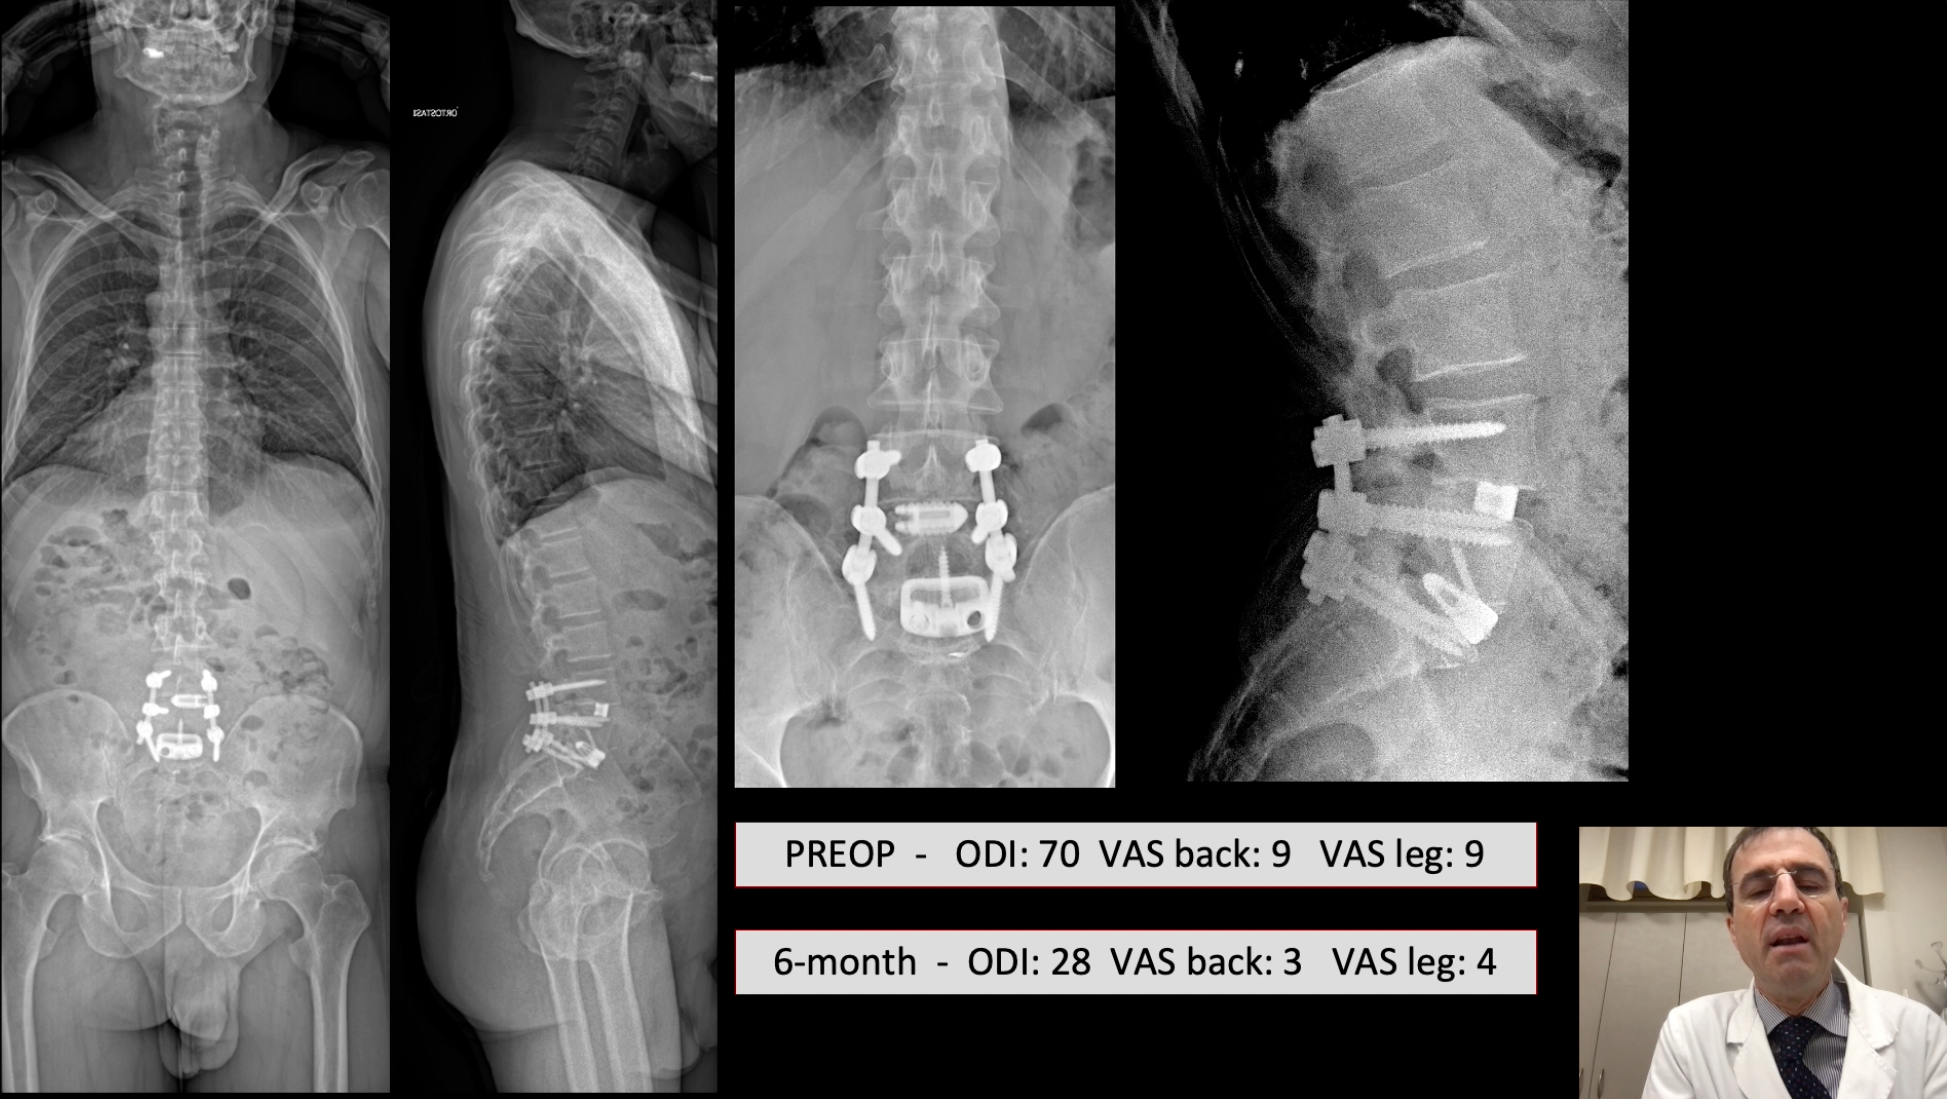

• Sagittal alignment correction and reconstruction of lumbar posttraumatic kyphosi

Sagittal alignment correction and reconstruction of lumbar posttraumatic kyphosis via MIS lateral approach

Berjano Pedro MD, PhD

GSpine4

IRCCS Ospedale Galeazzi Sant'Ambrogio

Milan, Italy

Project 12-018

Sagittal alignment correction with anterior column reconstruction of lumbar post-traumatic ky...